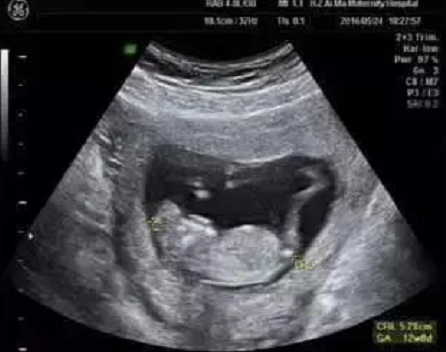

孕早期除了可以确定孕周、诊断死胎、异常妊娠、多胎妊娠,进行胎儿染色体异常的早期筛查与诊断之外,也具备进行严重结构畸形筛查的科学依据。

在为孕妈妈们做NT检查的同时,对于胎儿的结构也进行了详细的检查,并且发现了多例胎儿严重结构缺陷。

检查选在孕11~13周+6天进行,相当于头臀长45-84mm时测量,超过84mm检查结果会不准确。